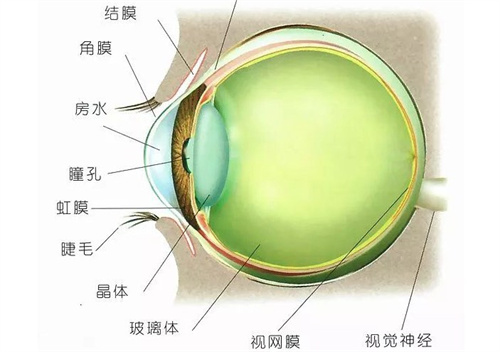

视网膜脱落的治疗方法有多种。对于尚未发生脱离的视网膜裂孔,可采用激光治疗,利用激光封闭裂孔,防止视网膜脱落。传统的巩膜环扎术和巩膜外加压术,适用于单纯的早期视网膜脱离。

而对于病情复杂的视网膜脱落,如伴有玻璃体混浊、牵拉等情况,玻璃体切割视网膜复位联合手术是常用的治疗方式。

这种手术对技术要求高,需要特殊的设备及术后护理。此外,渗出性视网膜脱离主要以治疗原发病为主。